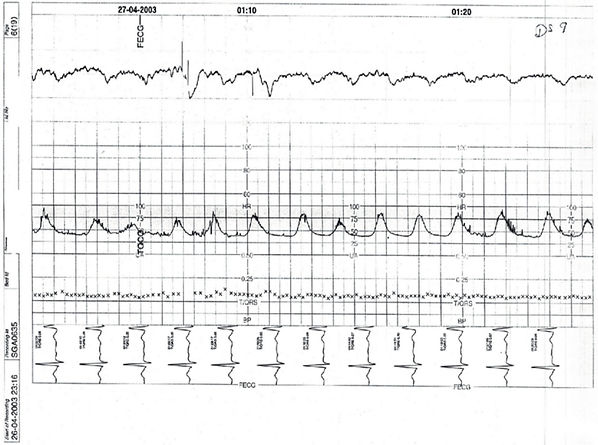

Das Team bereitet die Patientin für die notfallmässige Sectio vor. Die Anästhesie trifft ein, die Neonatologie kündigt ihre Ankunft an. Ein kontinuierliches CTG wird angelegt; die Hebamme dokumentiert lückenlos, während der Oberarzt eine knappe Lagebeurteilung verlangt.

Die Patientin bleibt hämodynamisch stabil, klagt jedoch über zunehmende Schmerzen. Das CTG läuft ohne Unterbruch und wird zur unmittelbaren Beurteilung freigegeben. „Wir brauchen eine klare Einordnung und eine kurze, belastbare Zusammenfassung“, sagt der Oberarzt.

Wie ist das CTG nach gängiger Systematik am zutreffendsten zu interpretieren?